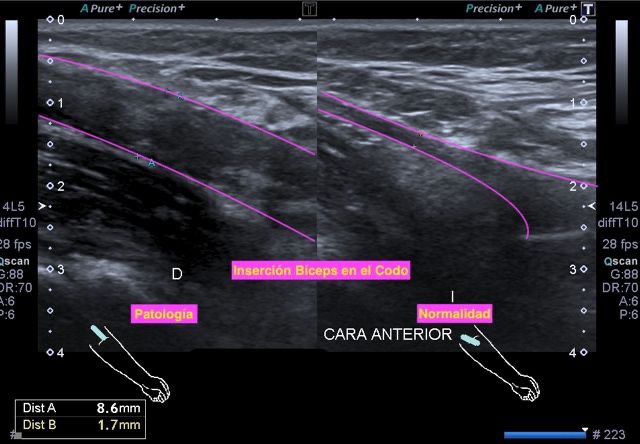

Detectar asimetrías significativas a tiempo puede ser fundamental para un diagnóstico y tratamiento tempranos. La ecografía es básica en este aspecto, permite una evaluación precisa de la simetría y asimetría anatómica de estructuras. Muchas veces al explorar una estructura par tenemos dudas si puede tener «algo»… comparar con el lado contralateral, muy a menudo nos va a resolver el problema, luego veremos algunos ejemplos muy claros.

En la ecografía muscular es una práctica habitual y muy sana, comparar. En casos de afectaciones unilaterales como las tendinopatías, roturas musculares, denervaciones…es muy saludable profesionalmente acudir a la compartiva para certificar hallazgos, te dejo algunos ejemplos para que puedas date cuenta de la importancia.